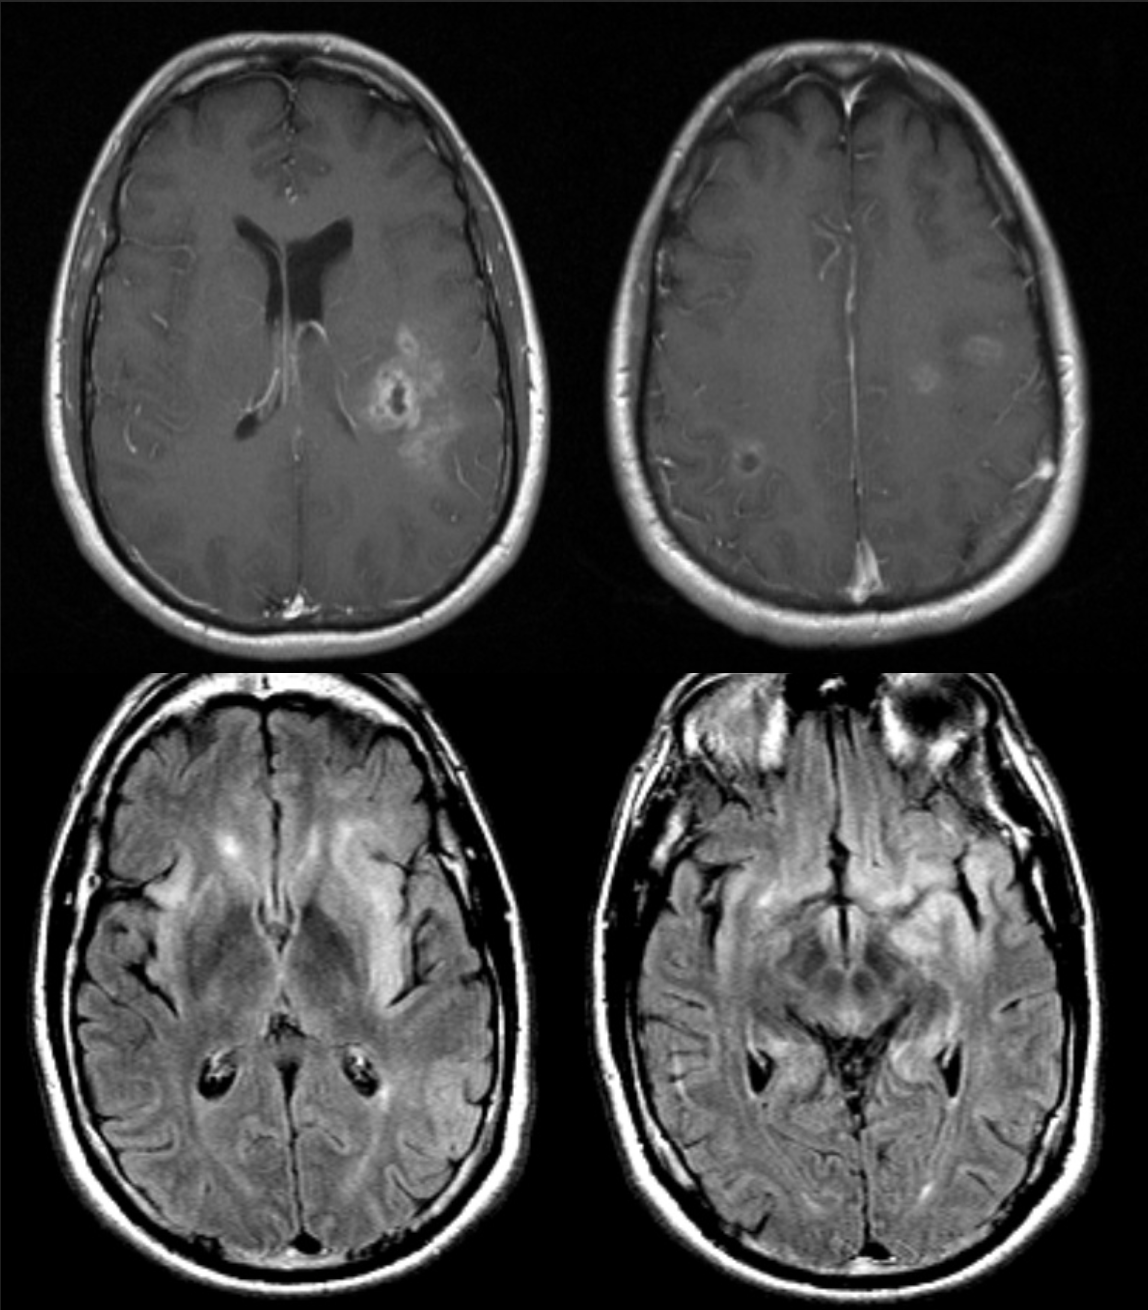

48 y/o M admitted for ETOH withdrawal, became encephalopathic and parkinsonized in hospital.

Central pontine and extrapontine myelinolysis